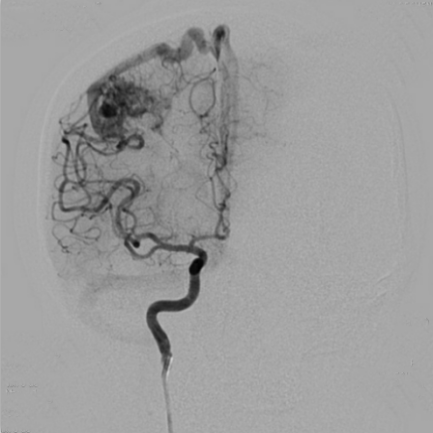

病例名称:颅内动静脉畸形的介入治疗 病史: 男性,62岁 主因“间断头疼半天”入院。 曝光模式及参数: DSA,减影3D 造影表现: DSA造影,造影提示右颈内动脉有巨大畸形血管团

为了观察动静脉畸形的栓塞效果,术后行DSA造影。DSA造影显示畸形团基本消失,栓塞效果较好